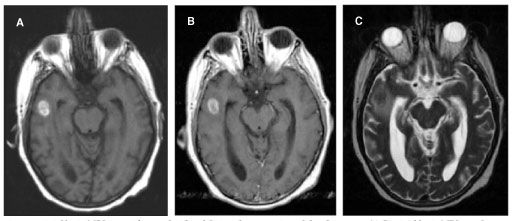

On the third hospital day, gadolinium MRI of the brain performed to evaluate anisocoria revealed a dominant 1.1 x 1.7-cm lesion with surrounding edema. Heme-sensitive sequencing demonstrated susceptibility artifacts around the lesion in the right temporal lobe consistent with associated hemorrhage (Figure 1). Subtle enhancement was also present, although no intense enhancement for pre-T1 hyperintense characteristics was seen (Figure 2, A and B). This dominant lesion was hyperintense on T2-weighted images consistent with surrounding edema and central hypointensity (Figure 2, C). This lesion also showed a smaller internal area of T2 hyperintensity that was not hyperintense on T1-weighted images. In addition, multiple tiny hemorrhagic lesions without marked edema were scattered throughout the cerebral white matter, notably in the corticomedullary junctions (Figure 3, A and B).

Figure 2.Axial brain MRI scan without and with gadolinium demonstrating subtle enhancement (A, B). Axial brain MRI scan demonstrating a T2 hyperintense mass consistent with edema and central hypointensity (C).